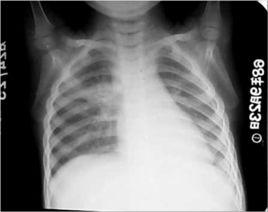

1.上葉下部或下葉上部片狀或類圓形模糊陰影,也可呈肺段或肺葉陰影。 2.同側肺門淋巴結增大。

3.肺內原發病灶與增大的肺門淋巴結之間可見索條狀陰影,即結核性淋巴管炎。

上述三者呈啞鈴形,又稱雙極期,為原發綜合徵典型表現,但這種徵象並不多見。如原發灶範圍較大,常可將結核性淋巴管炎和淋巴結炎掩蓋。